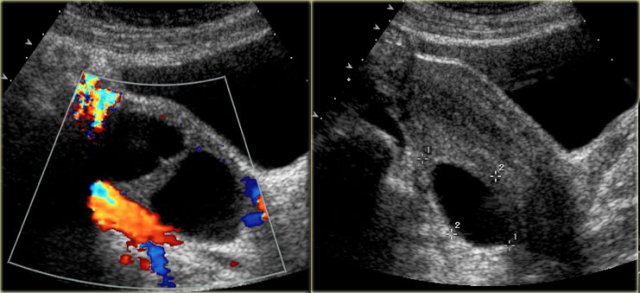

Corpus luteum cyst

A corpus luteum may seal and fill with fluid or blood, forming a corpus luteum cyst.

The transvaginal ultrasound images show a small complex ovarian cyst with wall vascularity on power Doppler analysis.

The characteristic circular Doppler appearance is called the 'ring of fire'.

Note, there is good through-transmission and no internal vascularity, consistent with a, partially involuted, corpus luteum cyst.

Another case with the typical the 'ring of fire' on ultrasound.

At pathologic examination the collapsed bloody cyst can be clearly seen.